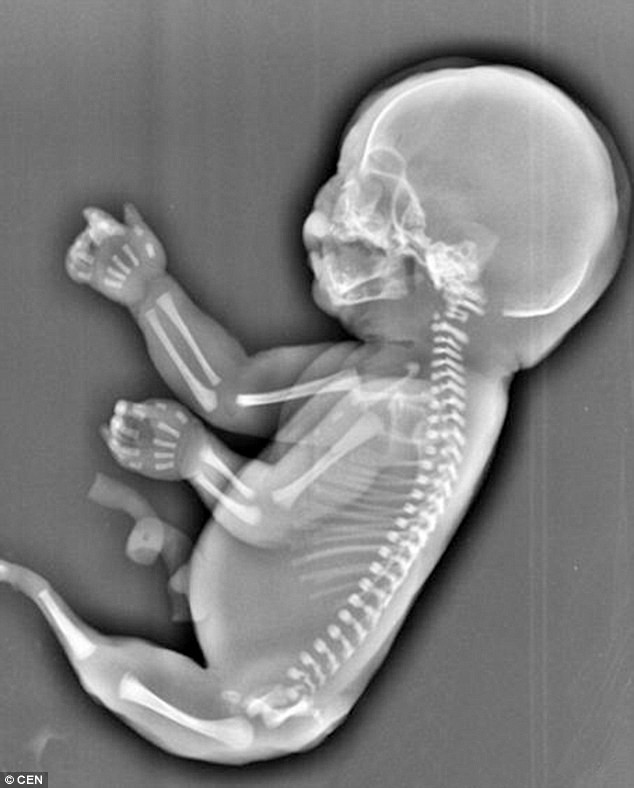

Bà mẹ đau đớn khi phát hiện mình đang mang thai "người cá" ảnh 1Bà mẹ trẻ đau lòng khi thấy hình ảnh về thai nhi. (Nguồn: CEN)

Theo đó, thai nhi sáu tháng tuổi trên không có hai chân và lại "mọc đuôi" giống như ​người cá.

Các bác sỹ cũng cho biết, thai nhi trên cũng không có bàng quang và hai lá gan phát triển không đồng đều.

​Theo các bác sỹ, thai nhi trên đã mắc phải hội chứng người cá, hay có tên khoa học là "Hội chứng Mermaid". Hội chứng này gây ra dị tật bẩm sinh hiếm gặp khi hai chân hợp nhất với nhau.

Nguyên nhân gây ra hội chứng Mermaid vẫn là một bí ẩn đối với y học thế giới. Tỷ lệ thai nhi mắc hội chứng này là 1/100.000./.